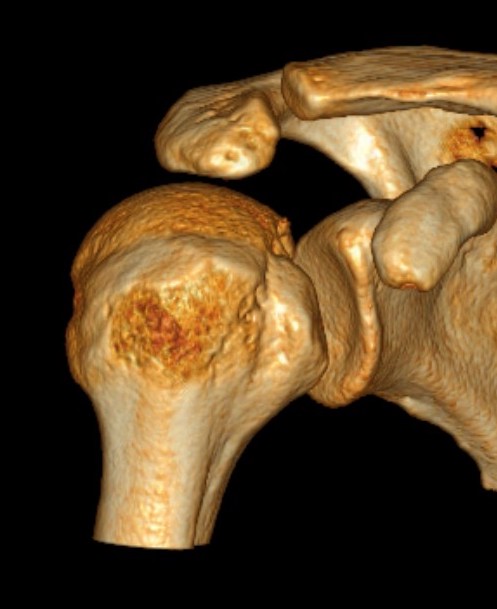

CT scan

Confirms dislocation

Reverse Hill Sachs

Humeral head defect

- caused by impaction of anterior humeral head on posterior glenoid

- intra-articular

- measured as a percentage of the articular surface